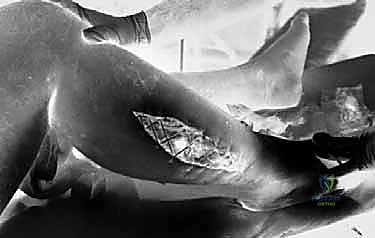

دليل شامل لعملية بضع اللفافة (Fasciotomy): خطوة بخطوة

عملية بضع اللفافة هي إجراء جراحي يهدف إلى شق الجلد واللفافة العميقة المحيطة بالحجرات العضلية بالكامل لفتحها، مما يسمح للعضلات بالتمدد وتخفيف الضغط الخانق واستعادة تدفق الدم.

التقنية الأكثر اعتمادًا وأمانًا والتي يفضلها الأستاذ الدكتور محمد هطيف لضمان تحرير كامل للحجرات الأربع هي تقنية الشق المزدوج (Two-Incision Technique)، والمعروفة أيضًا بتقنية مبارك وأوين (Mubarak and Owen).

الخطوة الرابعة: تقييم حيوية العضلات (Muscle Viability)

بعد فتح جميع الحجرات، يقوم الأستاذ الدكتور محمد هطيف بتقييم العضلات بناءً على 4 معايير (4 C's):

1. اللون (Color): هل عادت العضلات للونها الأحمر الوردي أم لا تزال داكنة/سوداء؟

2. الانقباض (Contractility): هل تنقبض العضلة عند لمسها بالمشرط الكهربائي؟

3. القوام (Consistency): هل العضلة مرنة أم صلبة كالمطاط الميت؟

4. النزيف (Capacity to bleed): هل تنزف العضلة عند خدشها؟

إذا كانت هناك عضلات ميتة تمامًا (نخرية)، يجب إزالتها (Debridement) لمنع التسمم والعدوى.